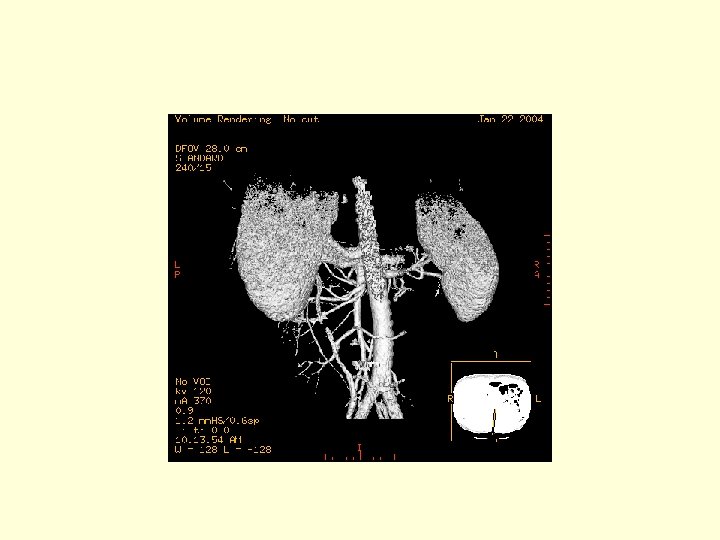

This is another 3 D image showing the vasculature of the SMA. Click through the next 20 frames to rotate the image.